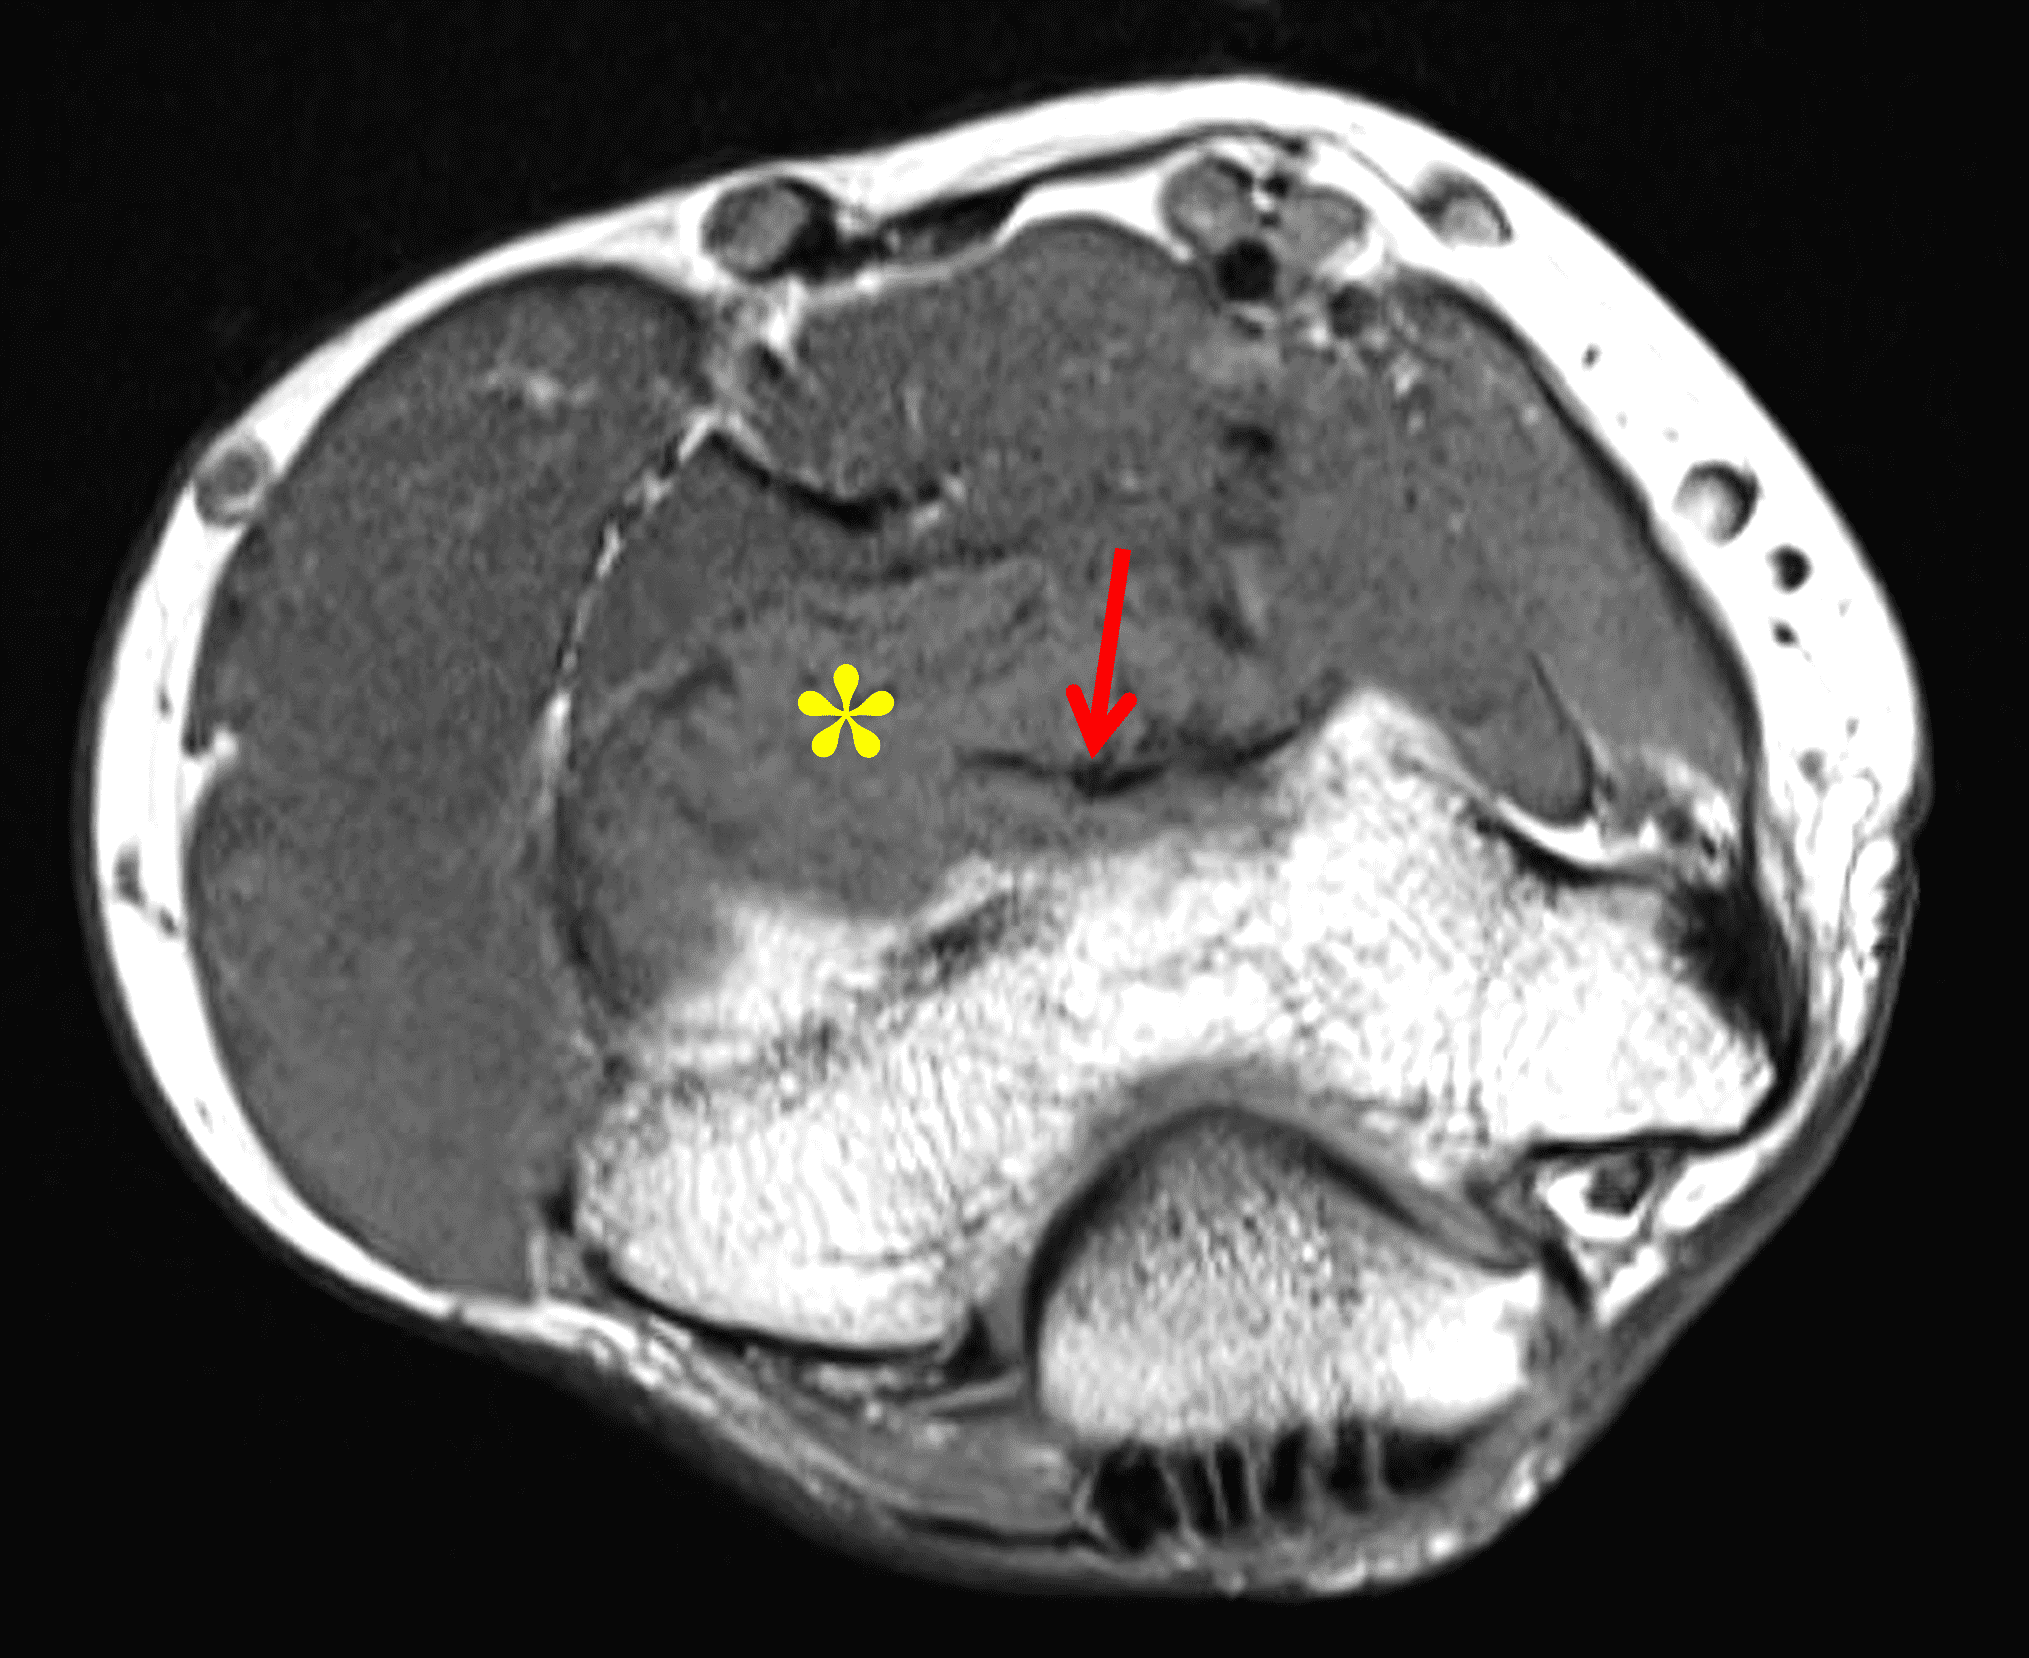

Rheumatoid arthritis (RA) is one of the most common chronic systemic autoimmune diseases, affecting 1% of the world population. It usually presents in the fourth through sixth decades, typically involving the wrists, hands and feet, and is more common in women. RA is characterized by inflammation of the synovial membrane, resulting in bone erosions and cartilage destruction.3,4,25,26,27

Radiographic findings include diffuse multicompartmental uniform joint space loss, marginal or central erosions, periarticular osteopenia and soft tissue swelling, usually without osteophytes or subchondral sclerosis.2-4,25-27 Inflammation results in pannus formation, which is characterized by a proliferative, hyperplastic vascular synovium that can cause erosions (Figure 14). On MRI, pannus is hypointense to intermediate signal on T1 and T2 sequences, demonstrating postcontrast enhancement of the active pannus. Rice bodies may also be present.2-4,25-27 While very rare, intra-articular rheumatoid nodules have been reported in the knee, wrist, elbow, ankle and sacrococcygeal joints.25,28

Figure 14: Rheumatoid arthritis in the shoulder joint. Axial fat-suppressed proton density-weighted image demonstrates diffuse intermediate to hyperintense signal synovial proliferation with rice bodies posteriorly (red arrow) and pannus anteriorly (yellow arrow). There is also generalized full-thickness glenohumeral cartilage loss without osteophyte formation.